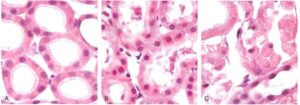

Al microscopio ottico è possibile osservare il rigonfiamento cellulare e la degenerazione grassa. Il rigonfiamento cellulare appare quando la cellula è incapace di mantenere l’omeostasi dei liquidi e dei sali a causa della perdita di funzione delle pompe di membrana ATP-dipendenti. Il rigonfiamento cellulare è la prima manifestazione in quasi tutte le forme di danno cellulare. È più evidente a livello di singolo organo che appare pallido e rigonfio. La degenerazione grassa si ha con la comparsa di piccoli o grandi vacuoli di lipidi nel citoplasma in seguito ad ipossia e danno tossico.